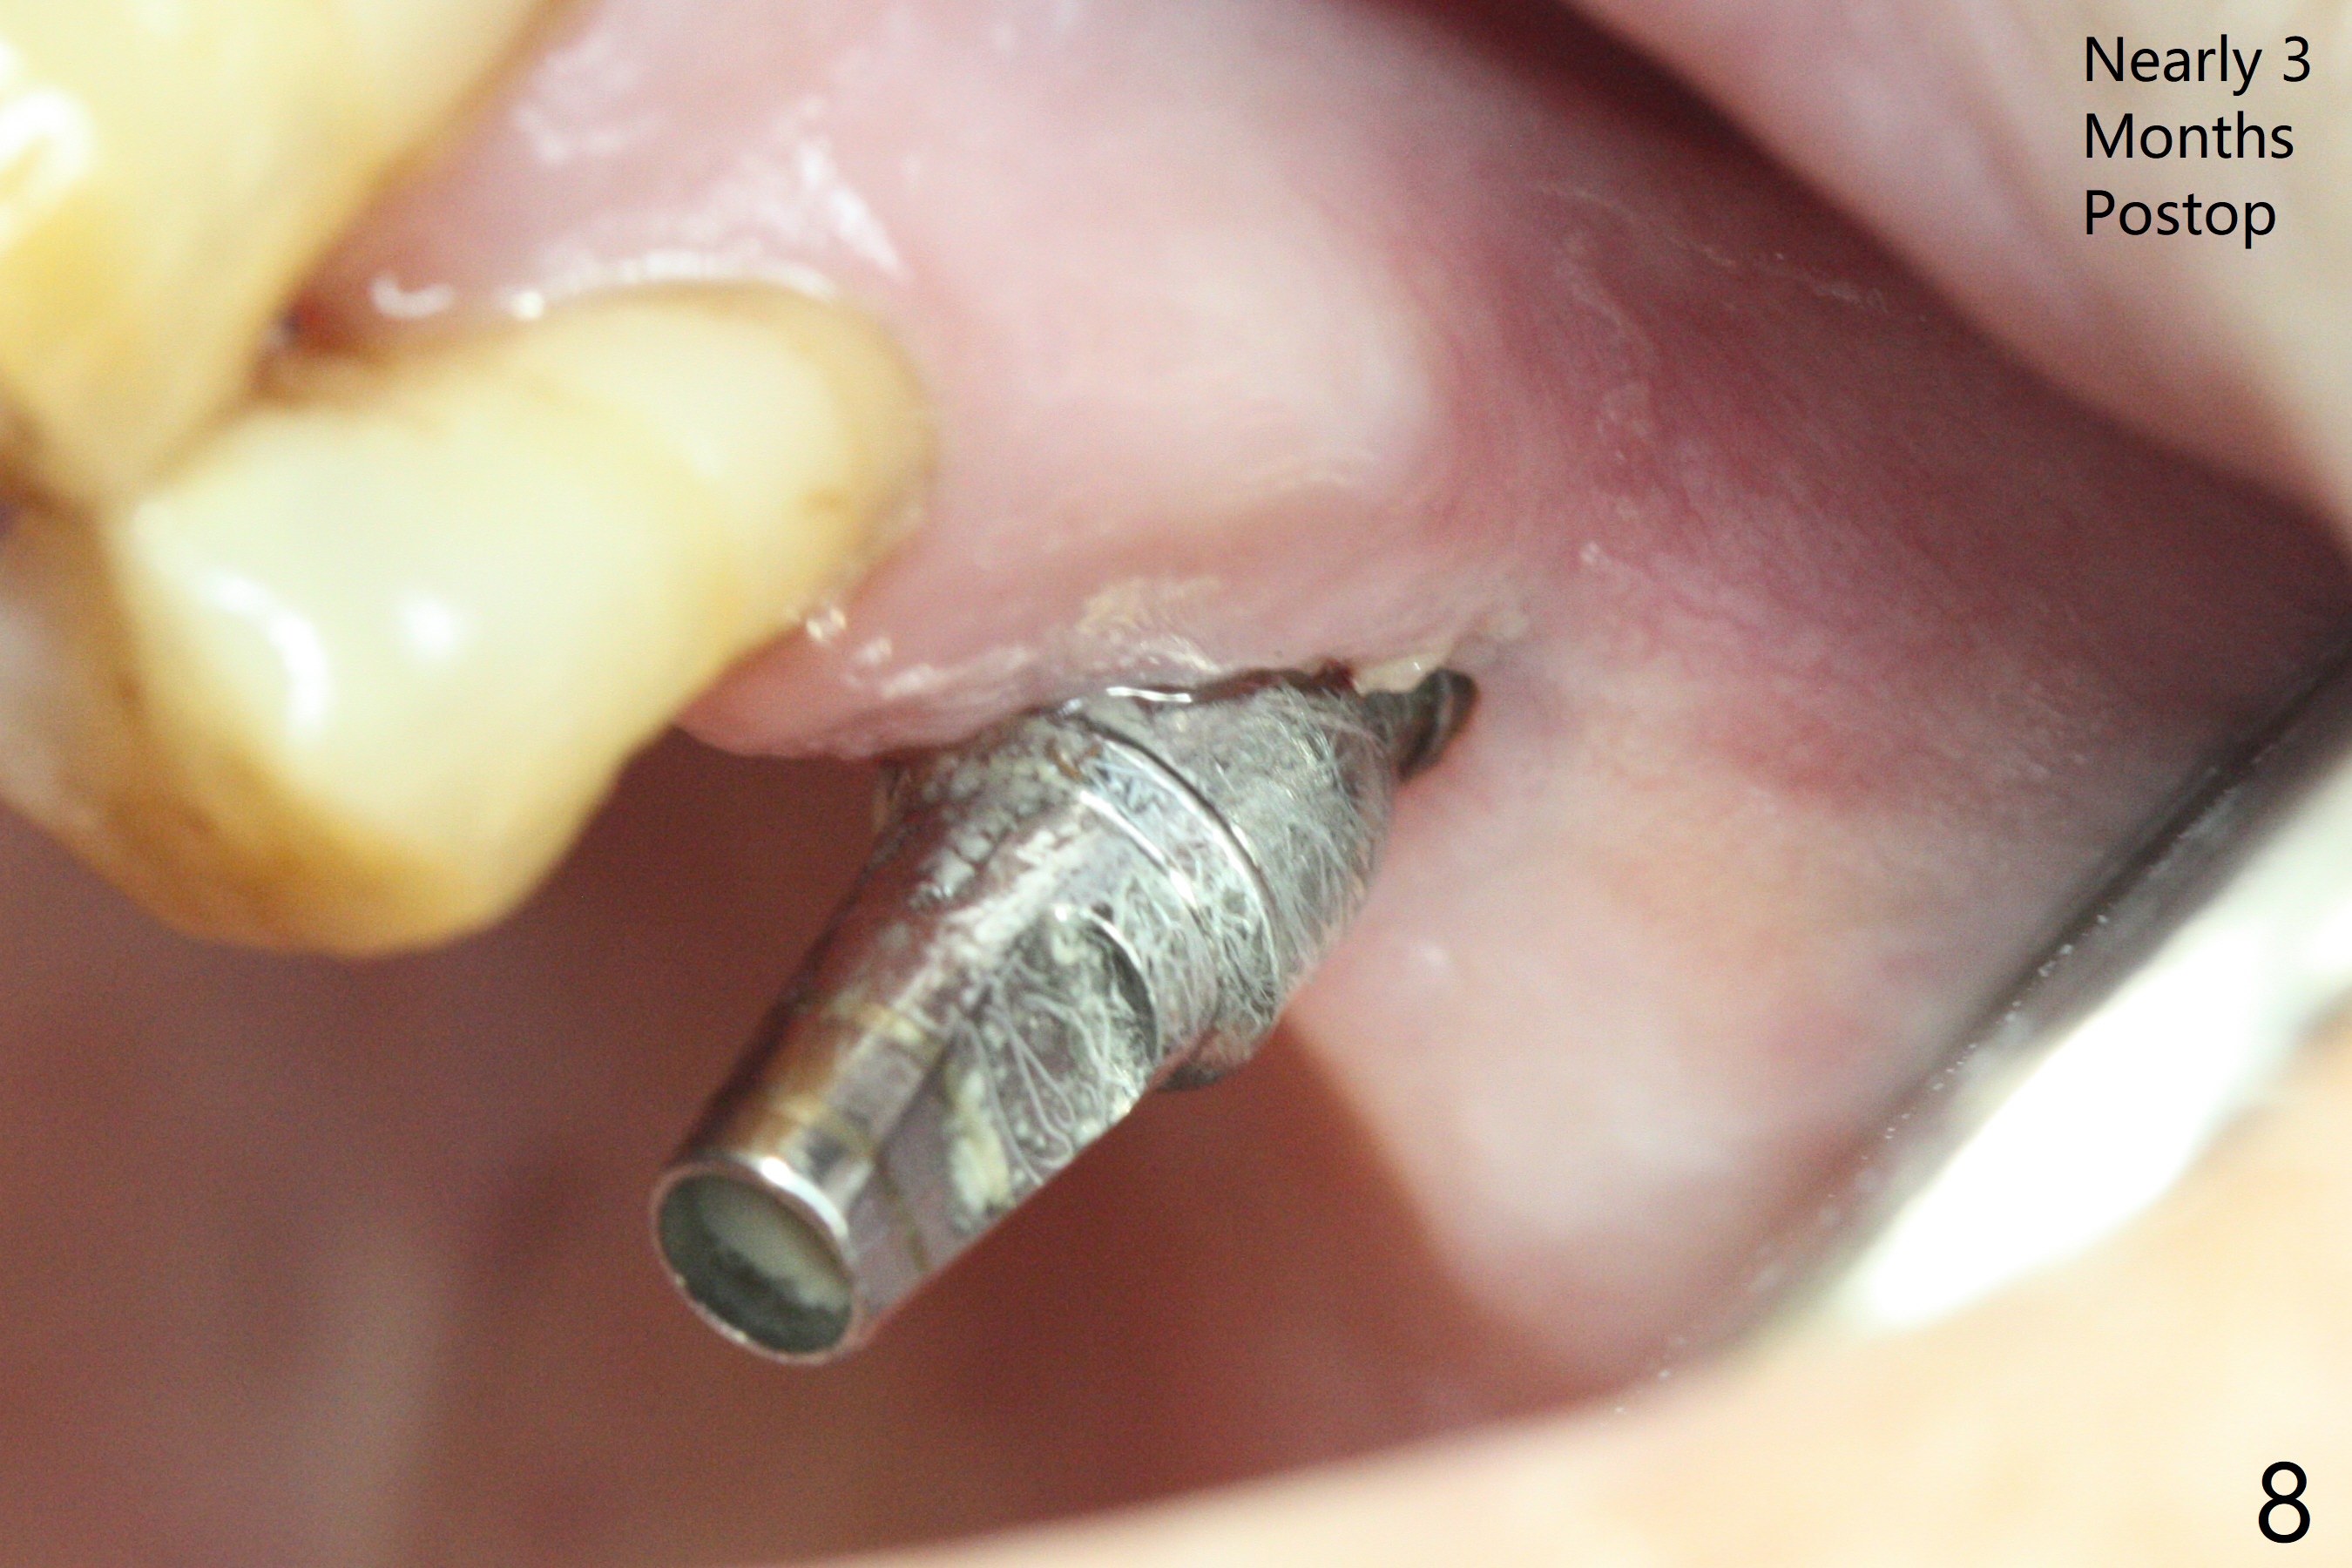

The septum is found to be pointed after extraction of the tooth #14 (Fig.1 *). The septum is flattened with Rongeur (Fig.2 *) prior to osteotomy. Because of interference of the mesial bone (Fig.3 *), osteotomy does not reach the depth with use of stopper. Without the latter, a 5x11.5 mm implant barely penetrates the sinus floor (Fig.4 (no postop nasal hemorrhage)). Also due to the mesial bone interference, a 6.5 mm abutment is not seated. Finally a 5.5x7(5) mm abutment is placed for an immediate provisional. Periodontal dressing is applied to cover the buccal repaired gingiva (Fig.5 *). There is minimal thread exposure after removal of the provisional nearly 2 months postop (Fig.6). The provisional does not return for easy self cleansing. In fact this is not an easy task, because of the posterior position (Fig.8 (after Piezo scaling)). The distal implant remains exposed; the abutment is removed and a healing screw is placed (Fig.9). The implant should have been subcrestal distally (Fig.7 <, nearly 3 months postop). One month later, the implant seems to be buried (Fig.10). The straight abutment is changed to an angled one (4.5 x15 degree A (5) mm) before impression retake (Fig.11,12 (<, dashed line: access hole)). The implant should have been placed more mesial (Fig.13). Surgical guide is needed. There is no implant exposure clinically or in CBCT sections 1 year 2 months post cementaton (Fig.14), although 3 D image suggests missing distopalatal plate (Fig.15).